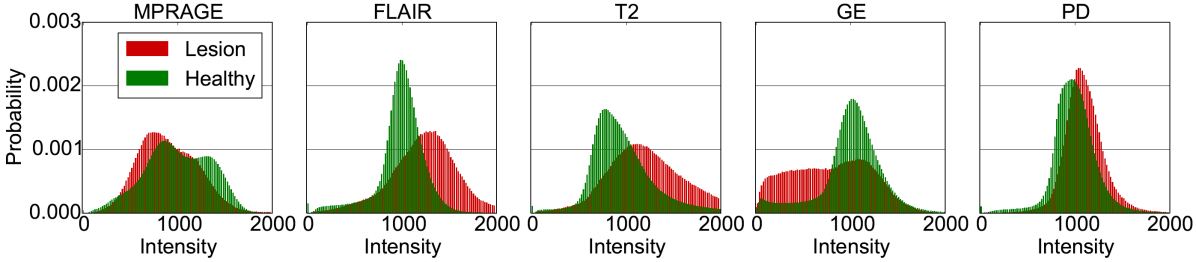

Figure 1 illustrates some of the challenges that arise when devising a computational approach for the task of automatic lesion segmentation. The figure summarizes statistics and shows examples of brain lesions in the case of TBI, but is representative of other pathologies such as brain tumors and ischemic stroke. Lesions can occur at multiple sites, with varying shapes and sizes, and their image intensity profiles largely overlap with non-affected, healthy parts of the brain or lesions which are not in the focus of interest. For example, stroke and MS lesions have a similar hyper-intense appearance in FLAIR sequences as other WMLs (Mitra et al. (2014); Schmidt et al. (2012)). It is generally difficult to derive statistical prior information about lesion shape and appearance. On the other hand, in some applications there is an expectation on the spatial configuration of segmentation labels, for example there is a hierarchical layout of sub-components in brain tumors. Ideally, a computational approach is able to adjust itself to application specific characteristics by learning from a set of a few example images.